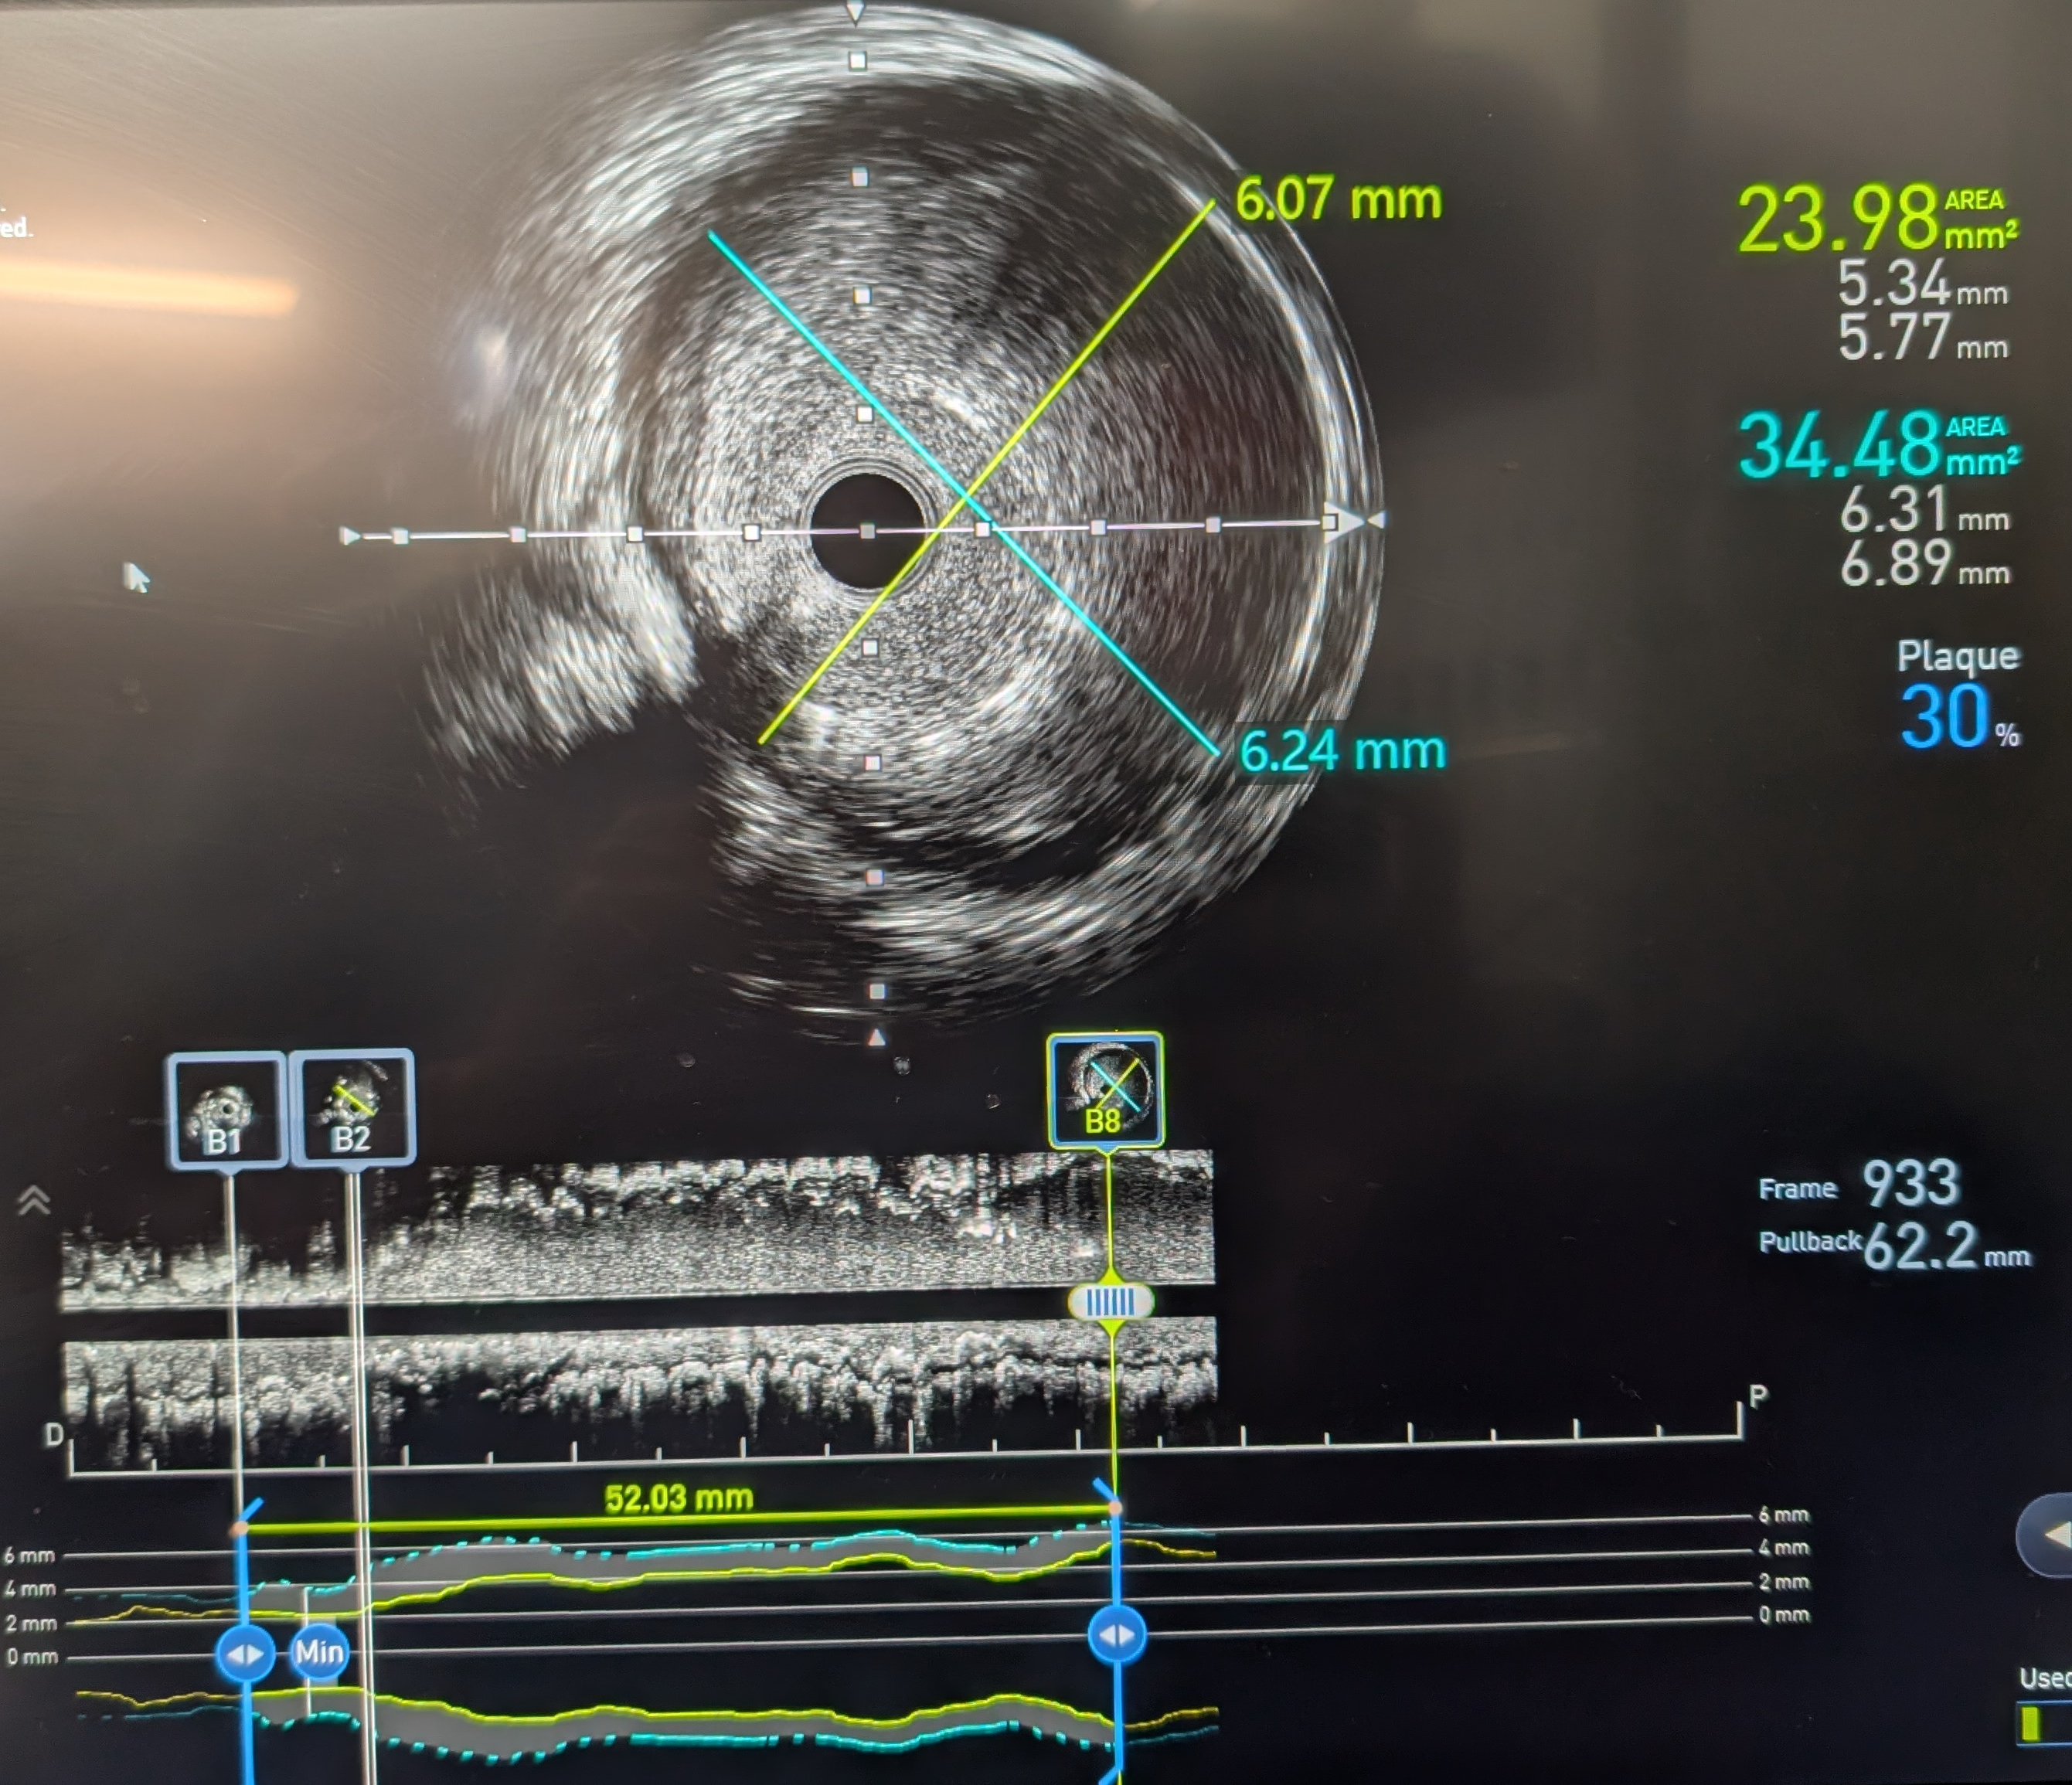

Intracoronary GTN was given after predilatation. IVUS showed mostly fibrous plaque with plaque extending from the distal RCA to the proximal RPDA. Reference diameters (EEL) were 4.5mm proximally in the distal RCA and 2.75mm distally in the RPDA. PCI to the distal RCA to RPDA with a provisional approach, using a stent with high postdilatation limits across the bifurcation.

PCI was performed with a 7Fr JR4 Guide with wires in the RPDA and RPL. Lesion was predilated and stented with a 2.75x33m DES and postdilated with a 4.5mm NC proximal to the RCA bifurcation. IVUS showed underexpansion distally and severe malapposition proximally hence the stent was further postdilated with 2.75mm NC distally and 4.5mm in the distal RCA. ClearStent showed unravelling of the stent, which was confirmed on IVUS with a new total stent length of 52mm. The distal RCA diameter had grown in size to 5mm at the site of the proximal stent edge. A 4.5x24mm DES was implanted in the distal RCA to cover the unravelled stent struts, which was postdilated with a 5mm NC balloon. Final IVUS showed the stent to have adequate apposition with no immediate complications.